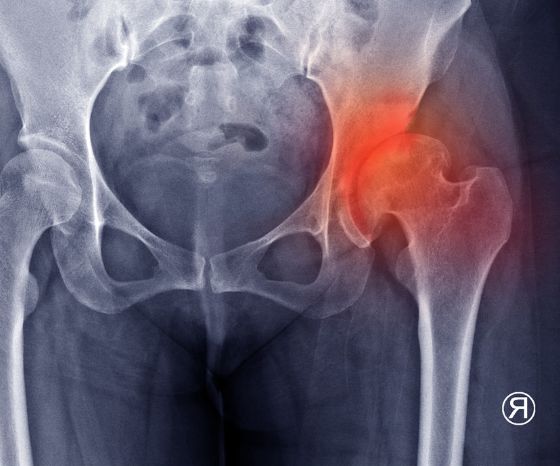

によると フェルソンら (2005)変形性関節症の典型的な特徴は、関節軟骨の質と厚さの組織学的変化である。 関節軟骨が減少すると、軟骨下骨が肥大し、関節面の端に骨棘が形成される。 もう一つの結果は、滑膜組織の慢性炎症である。 これらの変化はすべて、不規則な関節表面、骨の肥大、関節包の肥厚の可能性、そして最終的には水腫につながる。 その結果、関節腔の減少がレントゲン写真で確認できるため、「レントゲン性変形性関節症」とも呼ばれる。